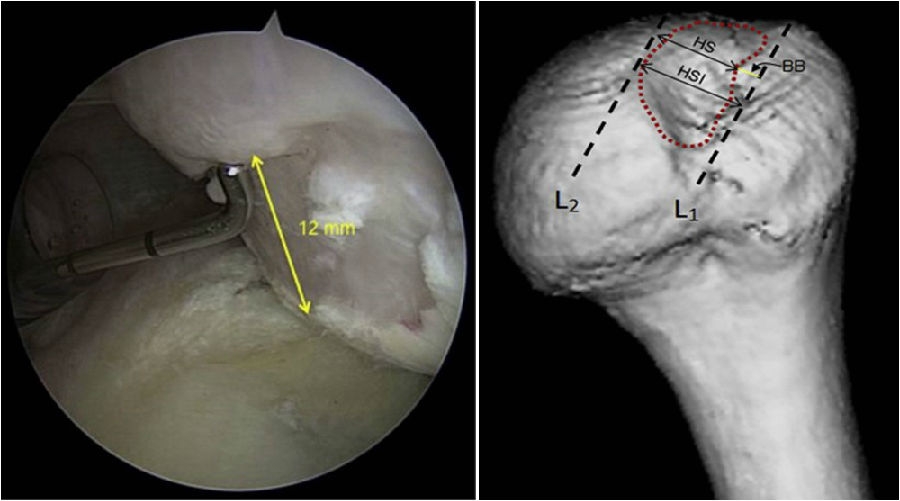

图31 D:15X2=30mm,d:15-10=5mm,83%D=24.9mm,d/D=16.7%

根据公式,可以计算出存在骨缺损的肩胛盂轨迹(0.83D-d),此例中的肩胛盂轨迹为0.83×30-5=19.9mm。

图32 Hill-Sachs损伤测量方式

上图为Hill-Sachs损伤的测量方式,采用前端为4mm的探钩,可以看到Hill-Sachs损伤的区域为3个探钩前端的跨度,因此HS为12mm。

评估报告提示:肩胛盂轨迹(Glenoid Track,GT)19.9mm,Hill-Sachs间距(Hill-Sachs Interval,HSI)24mm。

图34  BB=12

骨桥宽度的测量方式,采用前端为4mm宽的探钩测量,发现骨桥宽度正好为3个探钩前端的跨度,应为12mm。

计算Hill-Sachs间距(Hill-Sachs Interval,HIS)。这个间距应为Hill-Sachs损伤的宽度(HS)加上骨桥(Hill-Sachs损伤的外侧缘到肩袖止点)的宽度(BB),HSI:HS+BB=24mm。